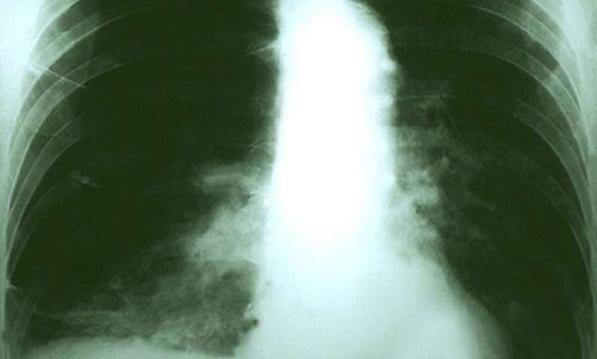

研究人员在经过平均 9.4 年的随访时间里,在 1,445,850 名参与者中确认了与肺癌相关的事件 18,822 例。总饱和脂肪摄入量高与增加的肺癌风险之间存在一定的联系(最高和最低风险比分别为:1.07 和 1.14,95% 的置信区间分别为:1.00-1.15,1.07-1.22;P 均 <0.001)。相对于曾经 / 从不吸烟人群,这种联系在当前还在抽烟的人群中更加紧密(风险比 1.23,95% 置信区间 1.13-1.35,P<0.001)。总饱和脂肪摄入量高,患鳞状细胞癌和小细胞癌症风险高于其他的组织学类型癌症(相对风险比分别为 1.61 和 1.40,95% 置信区间分别为 1.38-1.88、1.17-1.67,P 均 <0.001)。相反的,多不饱和脂肪摄入量高,则肺癌风险降低(风险比 0.92,95% 置信区间 0.87-0.98,P=0.2)。当饱和脂肪的能量有 5% 被多不饱和脂肪替代时,小细胞癌和鳞状细胞癌风险会降低 16 到 17 个百分点。

研究作者指出,“确认饮食脂肪的摄入(例如,用多不饱和脂肪替代饱和脂肪)可以降低癌症风险,尤其是降低那些吸烟者患鳞状细胞癌和小细胞癌的风险。”